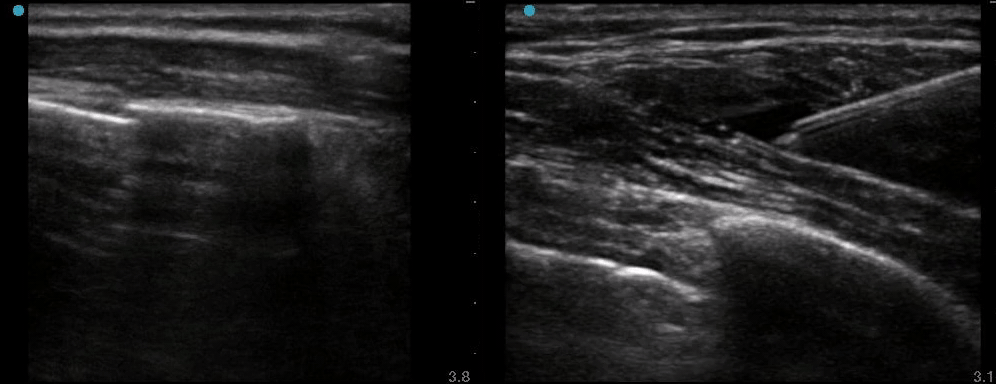

Left image - note the rib fracture

Right image - deposition of anesthetic between the lat dorsi muscle and serratus